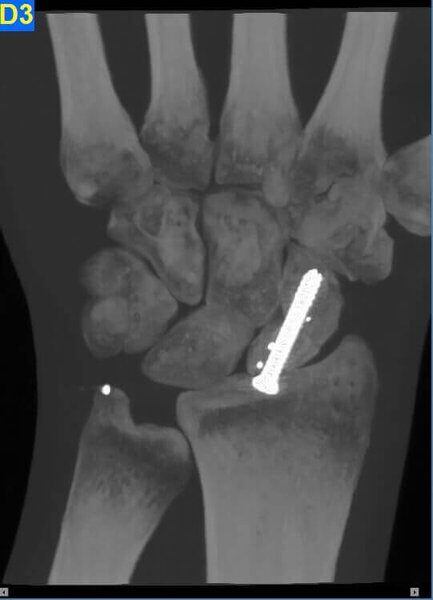

Fractura de escafoides con material de osteosíntesis.